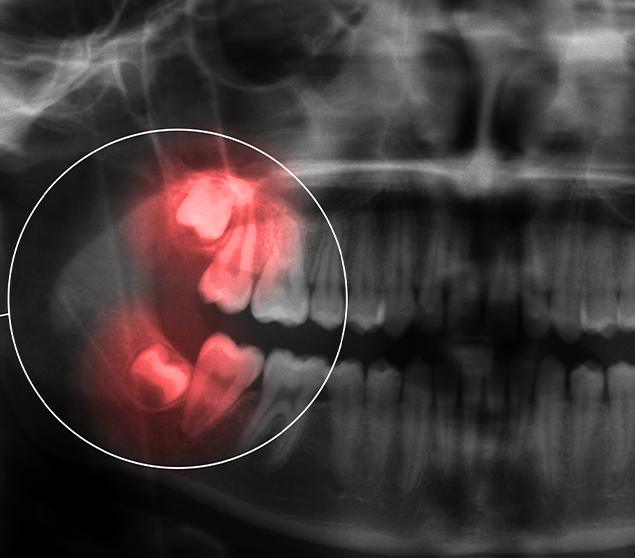

Before recommending extraction, our dental team completes a thorough assessment, which may include a clinical examination and dental X-rays. Findings and treatment options are reviewed clearly so you can make informed decisions about your care.